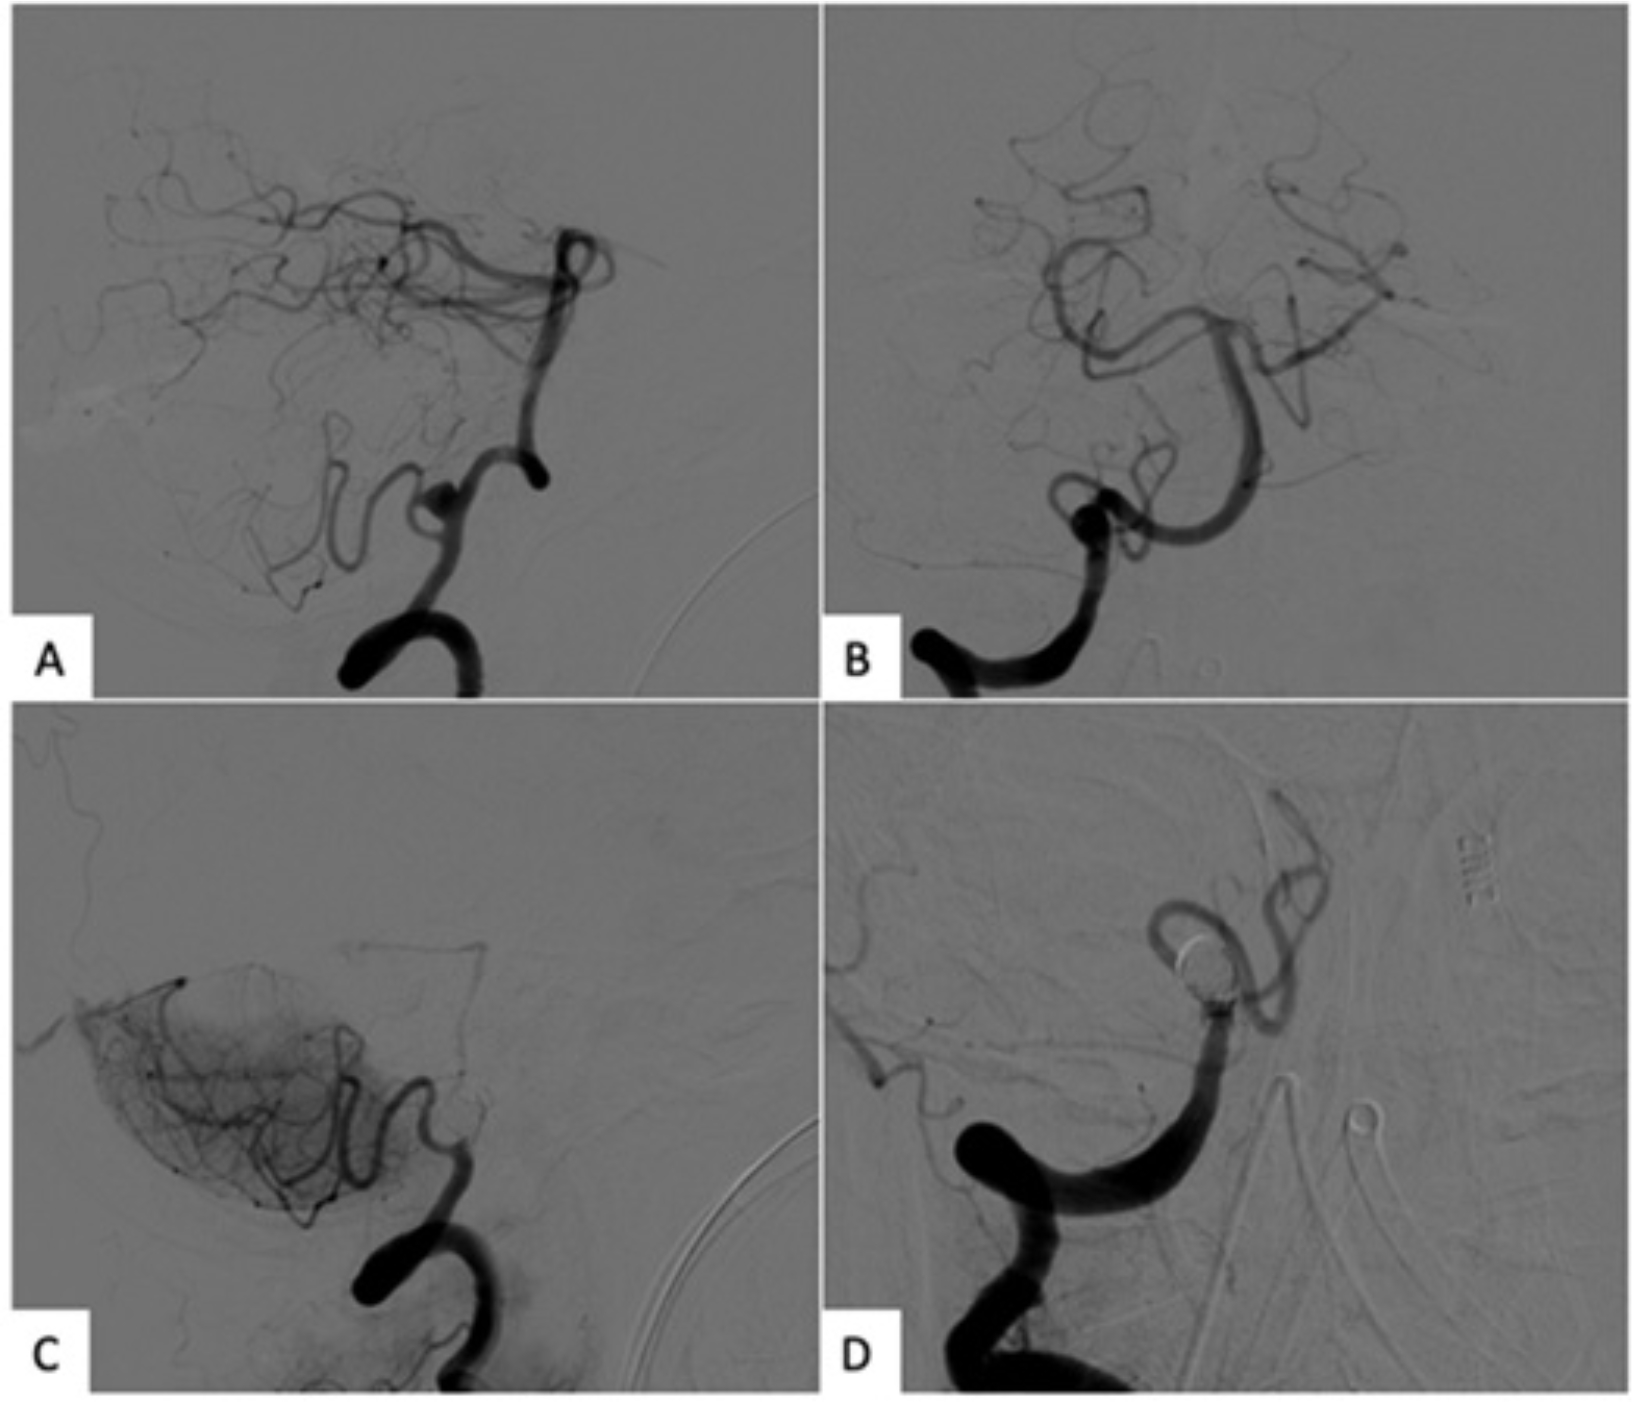

Abstract Image